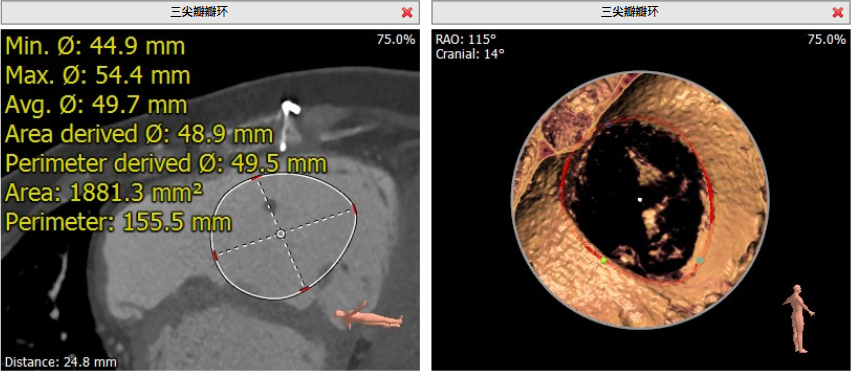

术前CT评估